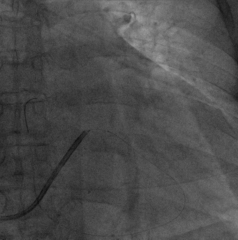

手术经过:首先冠脉造影延迟显影可见冠状窦开口及靶静脉大致走行

AP

LAO45